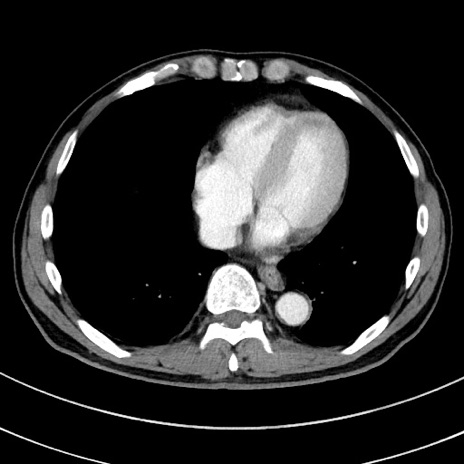

冠状断像

【症例】 60歳代男性

【主訴】 黒色吐物

【現病歴】 4日前から嘔気自覚、2日前の朝食後にも嘔気あり、自分で手で嘔吐反射起こし嘔吐したところ血が混ざっていたため受診。

【既往歴】 5年前汎発性腹膜炎を伴う急性虫垂炎で手術、高血圧、前立腺肥大症、高脂血症

【身体所見】 腹部正中に手術癩痕あり 腹部平坦・軟圧痛なし膨満感あり

【データ】WBC 8400、CRP 4.54